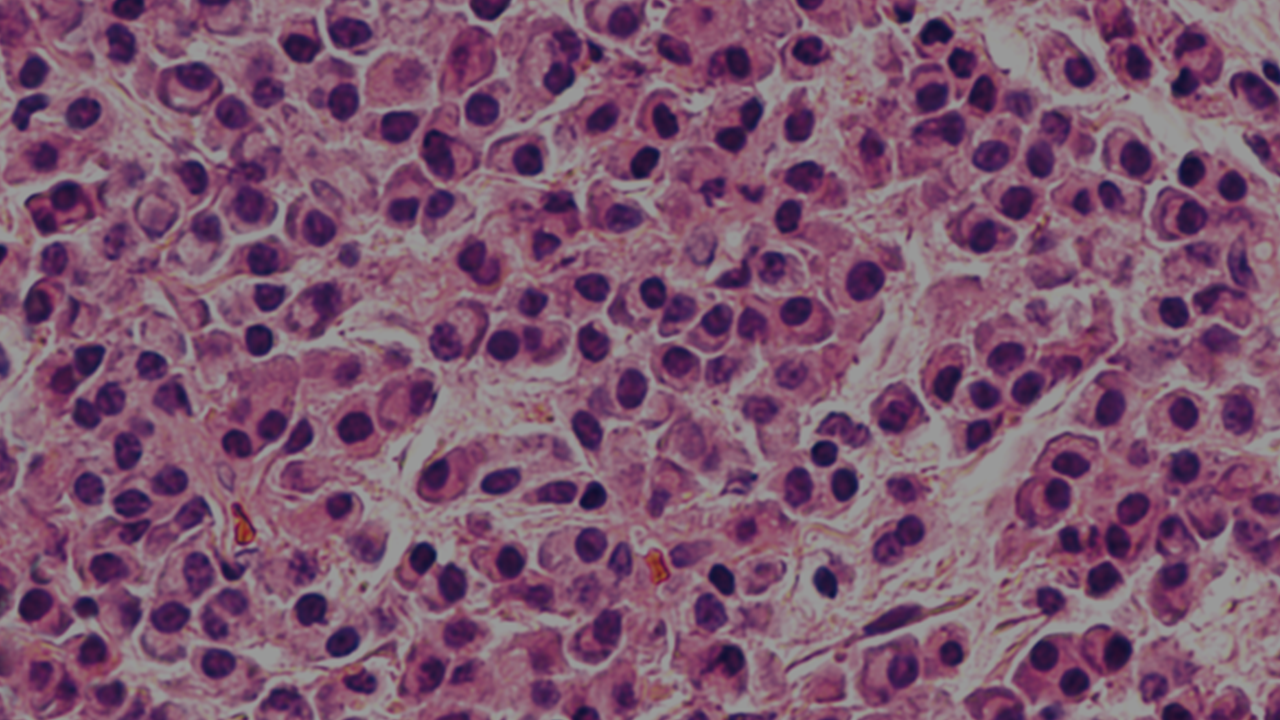

Early diagnosis is critical in MM.1 An array of diagnostic methods can be used to characterise a patient’s MM, allowing for individualised treatment and management.